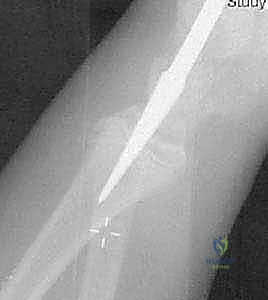

* الفكرة: بدلاً من فتح المرفق، يتم إجراء شق صغير جداً (لا يتعدى 1 سم) عند منطقة الرسغ (أسفل الكعبرة).

* يتم إدخال مسمار تيتانيوم مرن (Titanium Elastic Nail) داخل التجويف النخاعي لعظم الكعبرة، ودفع المسمار للأعلى حتى يصل إلى منطقة الكسر في المرفق.

* يتم استخدام طرف المسمار المنحني كـ "أداة دفع" لرفع رأس الكعبرة المكسور وإعادته إلى مكانه التشريحي الصحيح بدقة متناهية تحت جهاز الأشعة (C-arm).

* المزايا: لا يوجد فتح جراحي في المرفق، الحفاظ التام على التروية الدموية، ندبة شبه معدومة، وسرعة فائقة في التعافي.

صورة توضح دخول المسمار المرن عبر التجويف النخاعي لرد الكسر من الداخل دون المساس بمفصل المرفق.